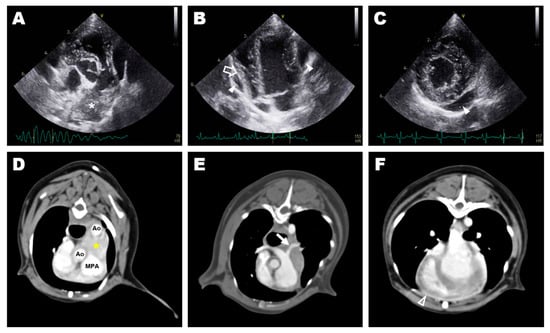

2. Case Presentation